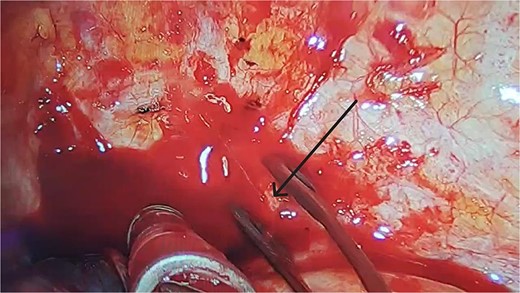

Immediate reoperation was performed. Upon re-entering the chest through the original incision, a substantial amount of blood clots were found. Active arterial bleeding was observed from a small vessel at the second intercostal space on the posterior chest wall, presuming to be the left second intercostal artery (Fig. 3). Hemostasis was achieved using electrocautery. Additionally, a protruding staple at the left upper lobe resection margin was noted, likely causing abrasion against the chest wall (Fig. 2B and C). The staple was removed, then the lung tissue was sutured using 4-0 non-absorbable monofilament. Hemostatic agents were applied to the bleeding sites. The total blood loss, including intraoperative and chest cavity blood, was ~2800 ml.

After clearing the blood clots, we observed a small artery on the surface of the posterior chest wall, around the second intercostal space, that was continuously bleeding in a jet-like manner (black arrow).